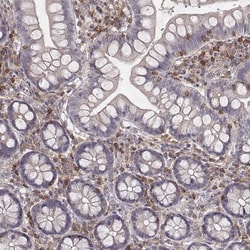

Invitrogen™ PILRA Polyclonal Antibody

Supplier: Invitrogen™ PA566000

| Immunohistochemistry (Paraffin) | |